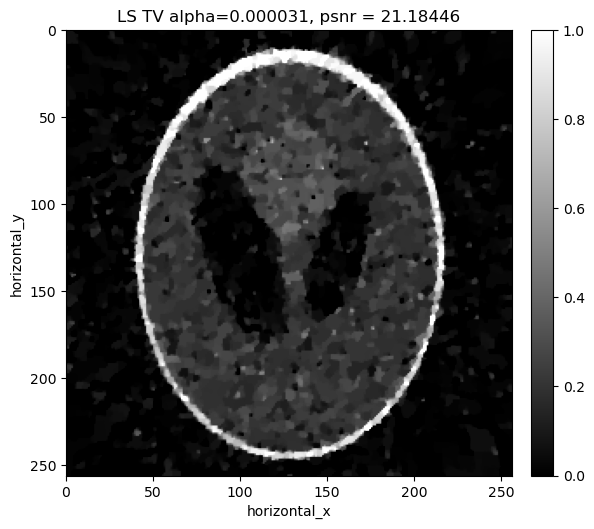

Reconstructing the noisy data using least squares with Total Variation regualrisation#

In addition to the least-square term, we considered a Total Variation Regulariser. So, for the LS-TV problem, we want to minimize the following:

\[||Y-Ax||_{2}^{2} + \alpha \, TV(x)\]

where \(\alpha\) is the regularization parameter that balances the two terms. In the next box, we search over a range of values of \(\alpha\) to find the best one for our data.

[22]:

if i%modulo == 0:

show2D([recon_ls_tv], ["LS TV alpha=%7.6f, psnr = %7.5f" % (alpha,psnr_ls_tv_alpha[i])], cmap=cmap,fix_range=(0,1), size=(10,10), origin='upper-left')

print("alpha=%7.6f, psnr= %5.3f" % (alpha,psnr_ls_tv_alpha[i]))

../../_images/demos_LS_WLS_KL_TotalVariation_34_0.png

alpha=0.000020, psnr= 17.222

alpha=0.000022, psnr= 18.315

alpha=0.000024, psnr= 19.247

alpha=0.000026, psnr= 20.028

alpha=0.000028, psnr= 20.667

../../_images/demos_LS_WLS_KL_TotalVariation_34_3.png

../../_images/demos_LS_WLS_KL_TotalVariation_34_4.png

alpha=0.000031, psnr= 21.184